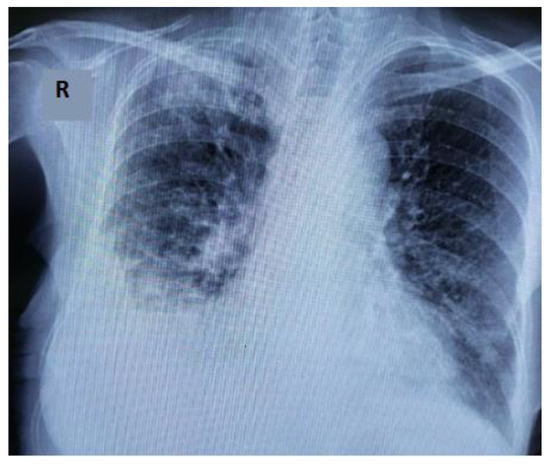

2. Clinical Experience—Case Report